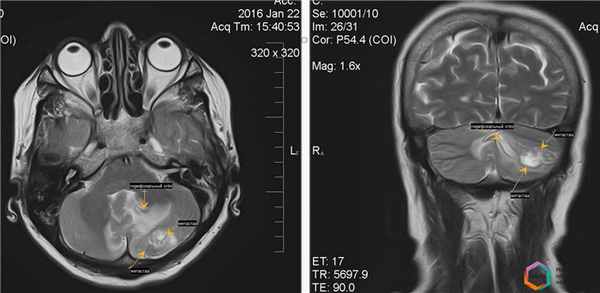

Клинический пример № 1:

Пациентка К., 56 лет, обратилась амбулаторно в кабинет магнитно-резонансной томографии по поводу головокружений, шаткости походки.

В анамнезе рак правой молочной железы, резекция молочной железы, прохождение курсов химиотерапии.

При исследовании головного мозга путем магнитно-резонансной томографии в различных режимах выявлен единичный метастатический очаг поражения головного мозга, локализованный в левом полушарии мозжечка, с наличием перифокального отека, распространяющегося на большую часть мозжечка. Данная локализация метастаза определяла симптоматику (головокружение, шаткость походки).

При проведении внутривенного контрастного усиления определены более точные размеры и границы метастатической опухоли.